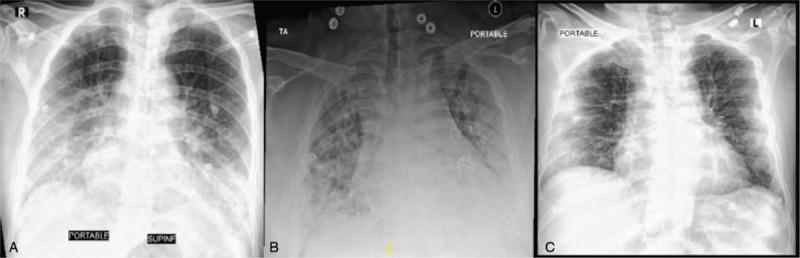

In this series, we are reporting 3 cases with different presentations of gastrointestinal perforation in the setting of COVID-19. Two patients were admitted with critical COVID-19 pneumonia, both required intensive care, intubation and mechanical ventilation. The first one was an elderly gentleman who had difficult weaning from mechanical ventilation and required tracheostomy. During his stay in intensive care unit, he developed Candidemia without clear source. After transfer to the ward, he developed lower gastrointestinal bleeding and found by imaging to have sealed perforated cecal mass with radiological signs of peritonitis. The second one was an obese young gentleman who was found incidentally to have air under diaphragm. Computed tomography showed severe pneumoperitoneum with cecal and gastric wall perforation. The third case was an elderly gentleman who presented with severe COVID-19 pneumonia along with symptoms and signs of acute abdomen who was confirmed by imaging to have sigmoid diverticulitis with perforation and abscess collection.

在本系列中,我们报告了 3 例 COVID-19 患者不同表现的胃肠道穿孔。2 例患者因重症 COVID-19 肺炎入院,均需要重症监护、插管和机械通气。第一位是一位老年男性,他很难从机械通气中脱机,需要进行气管切开术。在重症监护病房期间,他发生了无明确来源的念珠菌血症。转入病房后,他出现下消化道出血,并通过影像学检查发现盲肠穿孔伴有腹膜炎的影像学征象。第二位是一位肥胖的年轻男性,偶然发现膈肌下有气。计算机断层扫描显示严重的气腹,伴有盲肠和胃壁穿孔。第三位是一位老年男性,患有严重的 COVID-19 肺炎,伴有急性腹痛的症状和体征,影像学检查证实为乙状结肠憩室炎穿孔并伴有脓肿积聚。